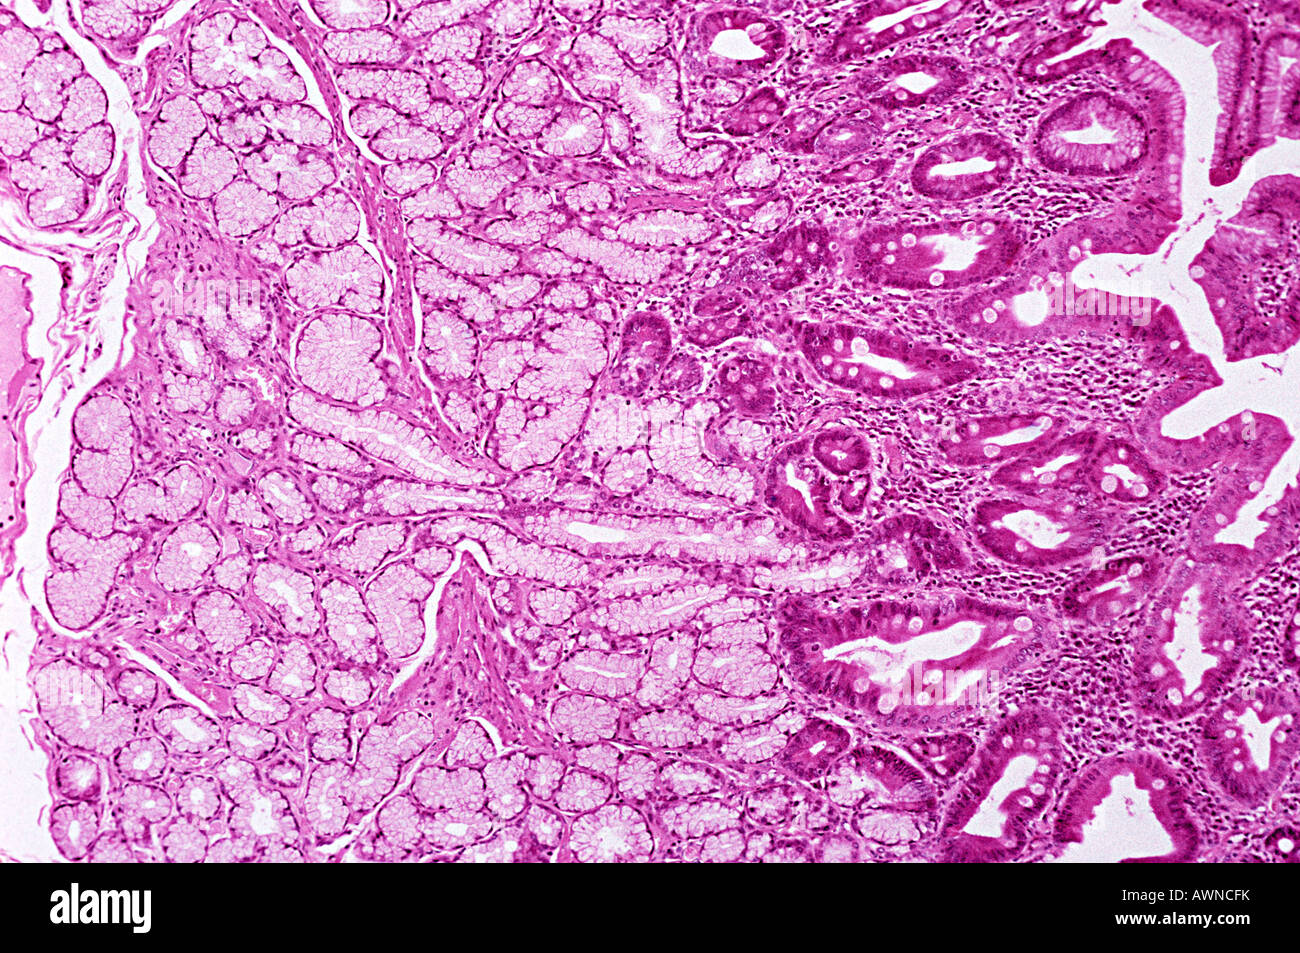

From www.alamy.com

First portion of the duodenum showing the Brunner glands located on the Brunner's Gland Explanation brunner's glands are unique to mammalian species and in eutherians are confined primarily to the submucosa of the. both brunner's glands, and the goblet cells in the duodenum secrete mucus. brunner's glands are unique to mammalian species and in eutherians are confined primarilyto the submucosa of the. brunner's glands are histologically indistinguishable from the glands located. Brunner's Gland Explanation.